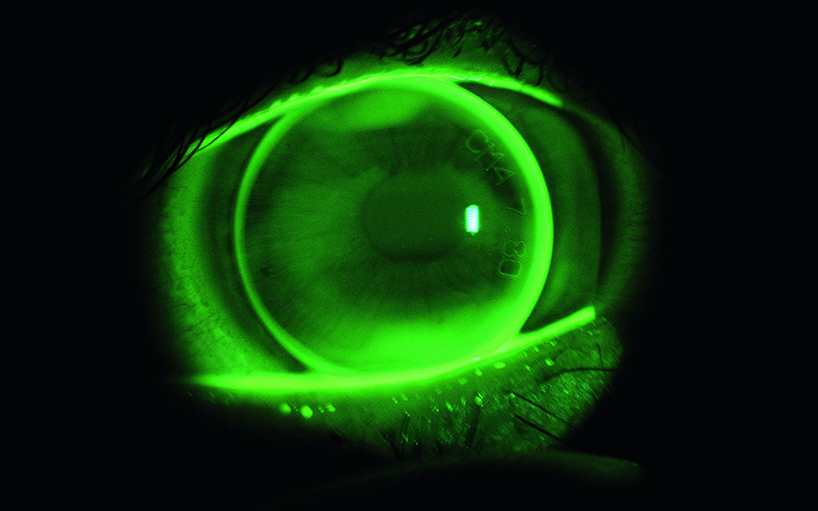

Développement d’une lentille de contact spéciale qui contient un capteur de pression pour la détermination de la pression oculaire.

L’Institut d’optométrie a pour mission de définir la conception des lentilles, principalement dans la perspective de la compatibilité physiologique et des capacités de mesure physiques.